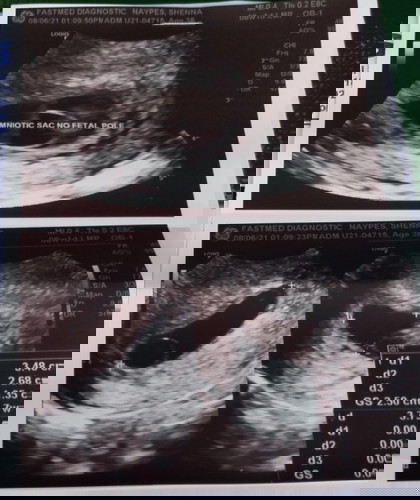

Anembryonic pregnancy Anu ibig sabihin?

Anembryonic pregnancy means hindi nadevelop yung embryo na magiging fetus. Ganun din po ako during my 2nd pregnancy... Consult your ob po.